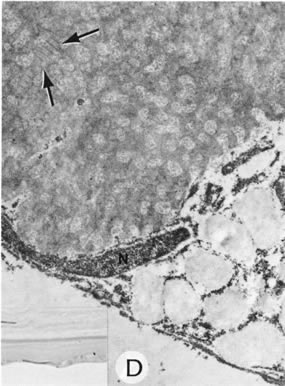

PETERS' ANOMALY

Peters' anomaly includes absence of central corneal endothelium, Descemet's membrane, and variable amounts of corneal stroma (Fig. 4). In most cases Bowman's membrane also is absent. Peters' anomaly may be caused by primary dysgenesis of the corneal endothelial mesoderm, primary dysgenesis of keratocyte and endothelial neural crest mesoderm, or secondary endothelial degeneration due to late anterior displacement of a normally developed crystalline lens.48 In addition, it has been suggested that abnormal apposition of an ectopic lens to the developing cornea during the second or third month of gestation may be the cause of exceptional cases of peripheral Peters' anomaly.49

Fig. 4. Peters' anomaly. A. Note the central corneal scar in the right and left eyes. The lens was adherent to the back of the corneal scar. Iris abnormalities also were present. B. The anterior segment shows a posterior corneal defect, a “top hat” appearance of the lens, and total adherence of the anterior surface of the iris to the cornea. C. High magnification shows termination of the endothelium and Descemet's membrane (arrow), corneal thinning, and localized absence of Bowman's membrane. The lens (lower left) is artifactually separated from the cornea. D. A PAS-positive membrane (lens capsule) is shown (top) adherent to the posterior corneal surface (arrow). The lens cortex (c) is artifactually separated from the rest of the lens (bottom). (Courtesy of SEI Photoarchives.) (B–D modified from Scheie HG, Yanoff M: Peter's anomaly and total posterior coloboma of retinal pigment epithelium and choroid. Arch Ophthalmol 87:525, 1972.)

Associated anterior segment anomalies include corectopia, iris hypoplasia, anterior polar cataract or other lens abnormalities, and iridocorneal adhesion. (Fig. 5) Corneal perforations secondary to Peters' anomaly have been reported at birth.50,51 Systemic anomalies include Potter's syndrome (agenesis of the urinary tract) and intestinal malrotation.52–54 Generally, no specific inheritance pattern has been noted, although a family that had an autosomal dominant inheritance pattern has been reported.55

Fig. 5. Peters' syndrome complicated by buphthalmos. The corneal anterior segment of the right eye has expanded because of the influence of increased intraocular pressure on scleral tissue that is still elastic in young people.

Histopathologic findings include absence of Descemet's membrane, corneal endothelium, and usually Bowman's membrane, as well as thinning of corneal stroma. The defects in Descemet's membrane, although usually single and central, may be multiple and isolated to the periphery or may be limited to an area of adhesion of iris.56 Descemet's membrane has been found to have embryonal ultrastructural characteristics combined with attenuated endothelium.57 The corneal stromal lamella are more irregular and closely packed when compared with normal. Immunohistochemical markers indicate that a normal complement of collagens type I, III, IV, V, and VI occurs in Peters' anomaly; however, an increased concentration may occur of the adhesive protein fibronectin, which is known to play a role in the embryologic development of the cornea.58–60